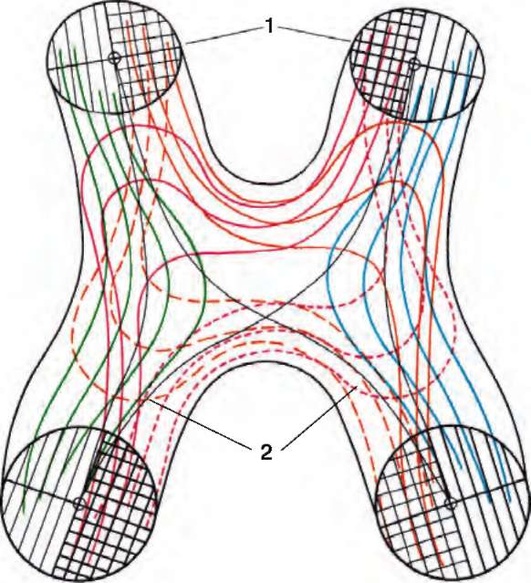

Рис. 2.5. Схематическое изображение хода нервных волокон в хиазме (по Traquair): 1 - зрительные нервы; 2 - зрительные тракты